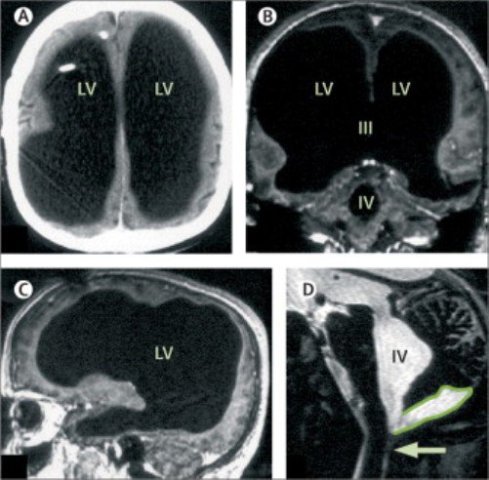

«Svopi.ru»–ի փոխանցմամբ՝ Մաթիե անունով 44–ամյա պետծառայողը ոտքի ցավի բողոքով դիմել է բուժհաստատություն։ Ամբողջական հետազոտությունից հետո բժիշկները պարզել են, որ տղամարդու կողմնային ուղեղային փորոքները գերլայնացած են, իսկ գանգի հետին խոռոչում բշտիկ կա։ Դրա պատճառով ողնուղեղային հեղուկը, որը պետք է շրջանառվի ուղեղով և հայտնվի արյունատար համակարգում, ողողել է տղամարդու ողջ գանգատուփը և շատ չնչին տեղ թողել գլխուղեղի համար։

Բժիշկներին Մաթիեն պատմել է, որ վաղ հասակում տառապել է հիդրոցեֆալիայով՝ գլխի մեջ ավելորդ հեղուկի կուտակումով։ Վեց ամսականում շունտավորմամբ նրա գլխից քաշել են ավելորդ հեղուկը, սակայն 14 տարեկանում ոտքի ցավեր են սկսվել, և շունտը հեռացրել են։

Մաթիեի ուղեղն այնքան փոքրիկ է, որ, կարելի է ասել, գրեթե չկա։ Ինչ վերաբերում է տղամարդու IQ–ին, ապա այն կազմում է 75 բալ (միջինը 100 է)։